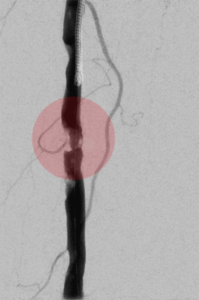

3. Stentimplantation – Einsetzen eines Stentes/ Gefäßstütze

Nach der Gefäßweitung kann durch Einrisse in den inneren Ablagerungen oder durch die Elastizität der Gefäßwand die Weitung nur ungenügend erfolgreich sein. Zur Stabilisierung des Befundes wird dann in diese Gefäßregion ein Stent eingesetzt. Dieser besteht aus einem feinen starren oder flexiblen Edelmetallgeflecht und kann auch mit Medikamenten gegen die Arteriosklerose oder zur Verhinderung der Bildung von Blutgerinnseln beschichtet sein.

Unter bestimmten Bedingungen, v.a. bei Verletzungen der Gefäße mit daraus resultierender Blutung oder lokalen Gefäßerweiterungen, werden Stents mit einer Ummantelung eingesetzt, die die Gefäßwand abdichten oder die Erweiterung überbrücken.